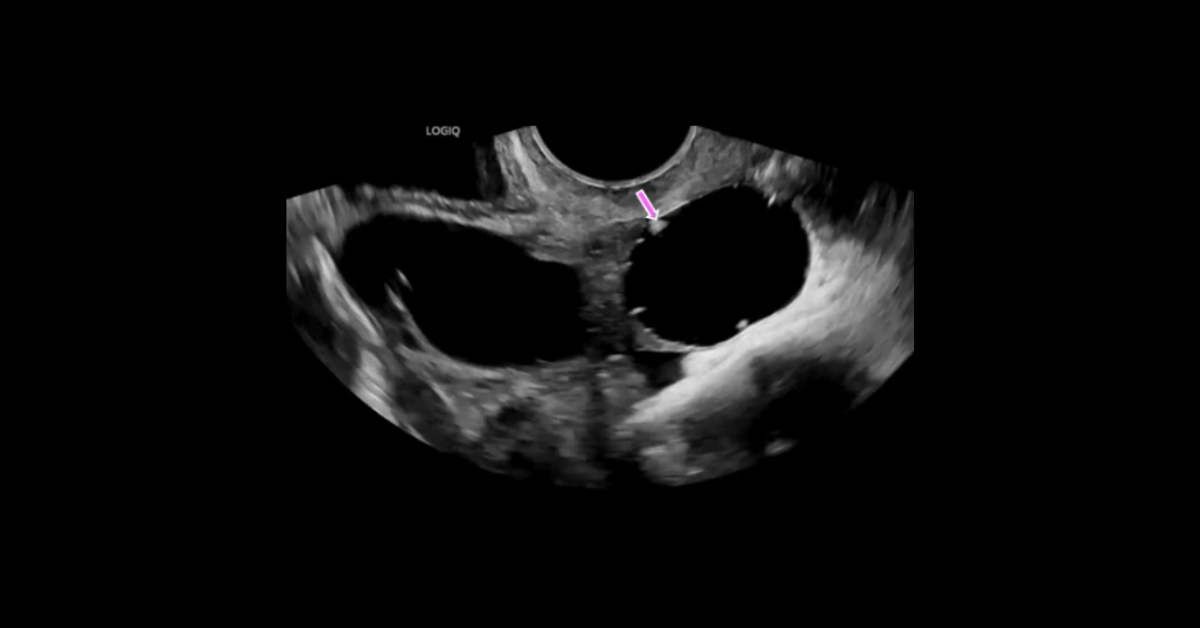

Ultrasound of Early Pregnancy

A collection of gynecology ultrasound studies presented in cine and screen shot formats, with initial presentation of each case enabling participants to render their own diagnoses followed by detailed discussion of each case.

1. Describe the typical US findings in a variety of gynecological abnormalities.

2. Understand the appearance of ultrasound artifacts.

3. List the differential possibilities for dilated fallopian tubes.